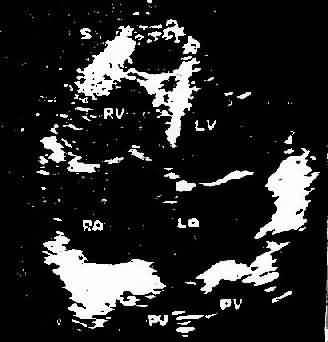

心尖四腔心切面二维超声心动图

图3-1-5 心尖四腔心切面二维超声心动图

A、照片 B、示意图

此是利用超声扫描技术 在荧光屏上显示超声波通过心脏各层结构如;心包、心肌、心内膜室间隔瓣膜和主动脉时发生的反射,借以观察心脏与大血管的搏动情况、房室的舒张和瓣膜开关的活动规律。目前常用的M型、B型超声心动图对二尖瓣、主动脉瓣的狭窄和关闭不全、三尖瓣狭窄,二尖瓣脱垂,特发性肥厚性主动脉瓣下狭窄,心房粘液瘤心包积液,房、室间隔缺损等的诊断均有较大的价值。此外,利用超声心动图测量房、室腔的大小,计算心排出量、射血分数等以了解左心室功能。近年来应用彩色多普勒血流显像探查瓣膜关闭不全的返流和先心病的分流量、提高了疾病诊断质量。(图3-1-4图3-1-5)